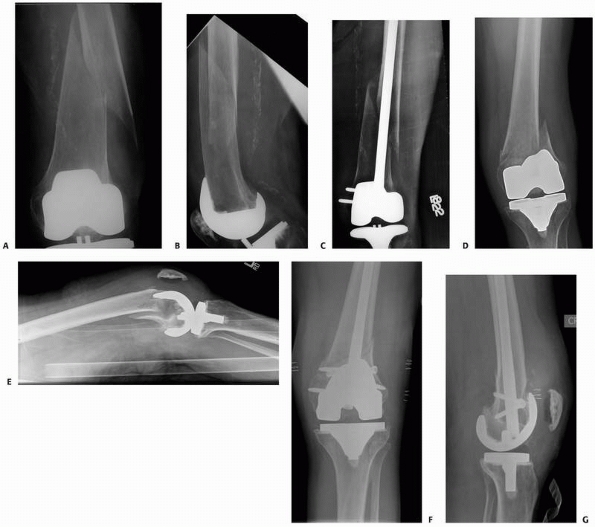

displacement and prosthesis stability (Fig. 21-13).85,133

Type I are stable fractures essentially nondisplaced and the

bone/prosthesis interface remains intact. Type II fractures are

displaced with an intact

interface and type III fractures have a loose or failing prosthesis regardless of the fracture displacement.

FIGURE 21-13

Classification scheme for periprosthetic fractures about the femoral component of the knee. Type I fractures are minimally displaced with an intact prosthesis bone interface, type II fractures are displaced but maintain an intact bone prosthesis interface, and type III fractures may be displaced or nondisplaced, but have a loose femoral component. (Modified from Lewis PL, Rorabeck CH. Periprosthetic fractures. In: Engh GA, Roabeck CH, eds. Revision total knee arthroplasty. Baltimore: Williams & Wilkins, 1997:275-295). |

account for the fracture location relative to the prosthesis, a factor

that has the potential to dictate treatment. The classification scheme

of Su et al. is useful in this vein where fractures are divided into

three types according to the fracture location relative to the proximal

border of the femoral component.151

Type I fractures are proximal to the femoral component, type II

originate at the proximal end of the component and extend proximally,

and type III extend distal to the proximal border of the femoral

component (Fig. 21-14).

![]() |

FIGURE 21-14

The Su classification of periprosthetic distal femur fractures accounts for location of the fracture relative to the femoral TKA component. |